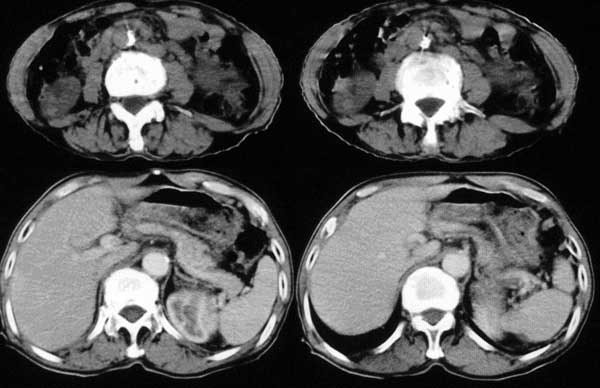

附肾脏平扫及增强片

手术是怎么做的,好像没做。右肾还有两个病灶。气管腔内的那个结节密度确实很低,考虑粘痰核应该没问题,若是新生物不会这么低。不过挂在前壁上了,少见!

肺及胸膜下多发结节影,胸椎及附件、肋骨破坏支持转移癌。气管内结节影支持痰核。肾脏ct应该是术前的吧?左肾内亦见一低密度灶,另外胰腺好像也不规则。不知术后结果如何?

左侧肾癌,腹膜后淋巴转移,肺及胸椎转移,右肾转移可能,气管内痰栓可能[壁可见]

左侧肾癌伴腹膜后淋巴结、胸椎、双肺内转移。